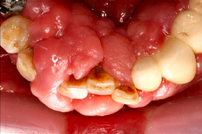

A 65-year-old female on antihypertensives and immunosuppressants presented with severe gum swelling, inability to chew, and difficulty maintaining oral hygiene. This led to multiple decayed and periodontally compromised teeth, worsening her overall condition.

- Non-surgical periodontal therapy was performed to reduce gingival inflammation and swelling

- Surgical removal of excessive gum tissues and extraction of multiple poor prognosis teeth were carried out as well

- She was kept under strict follow up and advised to comply with meticulous oral hygiene measures throughout treatment